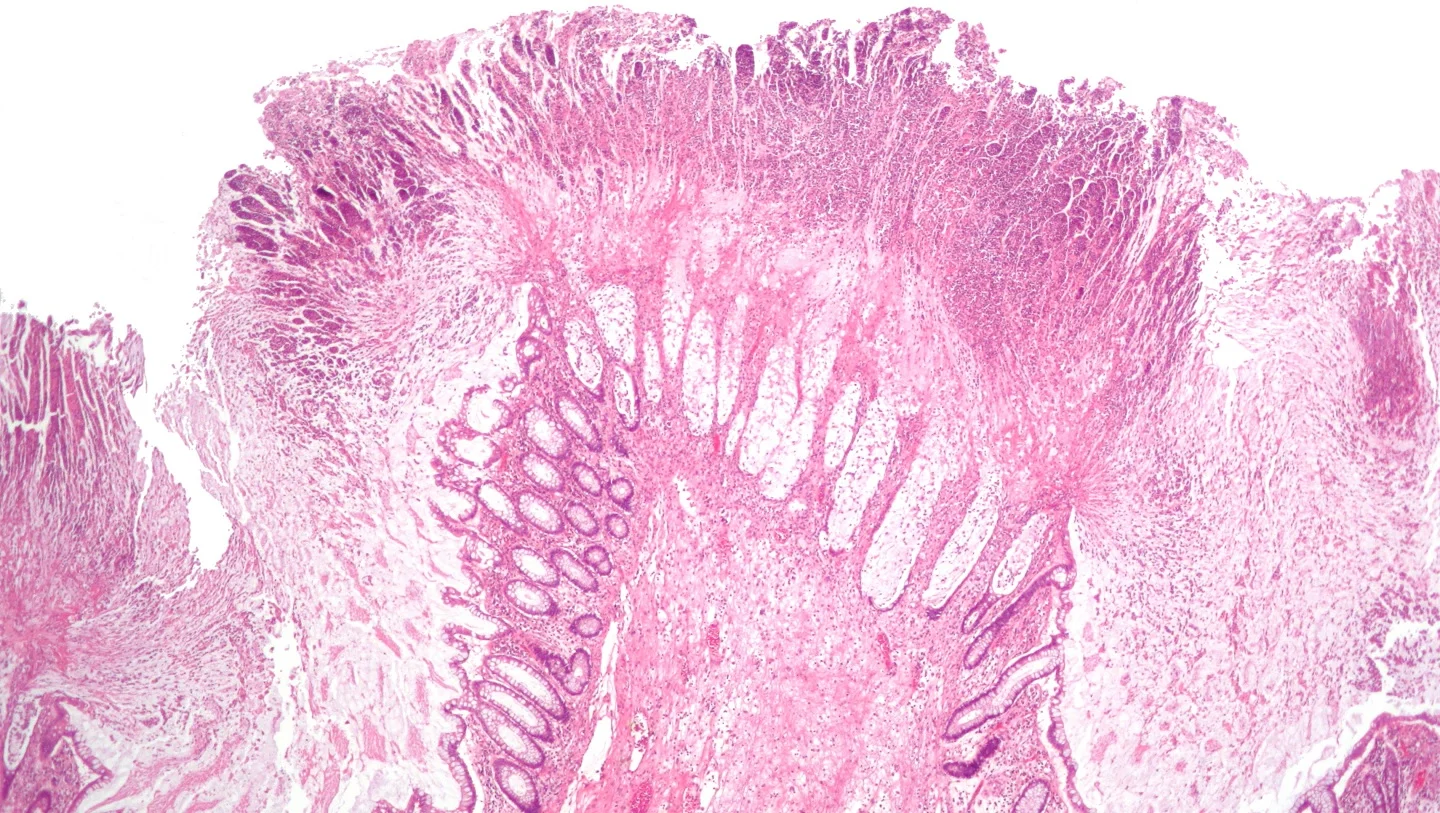

在Vowst之前,对于经常复发艰难梭菌感染的病人,一般采用结肠镜移植粪便微生物群来平衡病人体内的肠道微生物群落。

Vowst是由健康合格的人捐赠的粪便制成。粪便经乙醇处理过后,剩下的厚壁菌门菌种的纯化细菌孢子可以影响艰难梭菌疾病的发生。在1b期的临床试验中,有86.7%的患者达到试验主要终点。